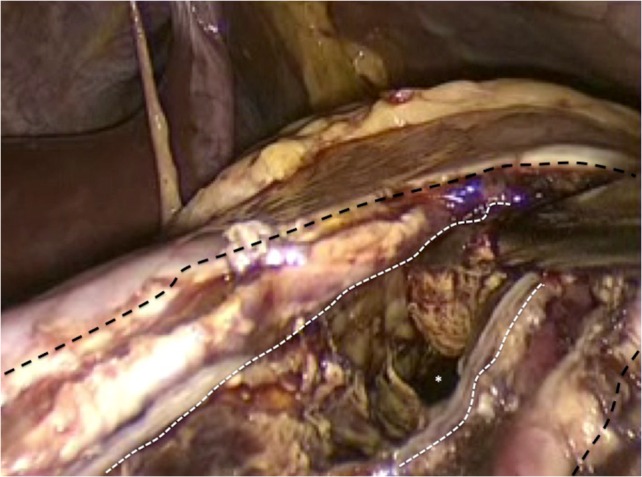

Figure 6:

The incision at the anterior stomach wall (outlined by the broken black line) is retracted to allow access to the posterior stomach wall. An endo-GIA stapler has been fired to create a stapled anastomosis (outlined by the broken white line) between the posterior wall of the stomach and the anterior wall of the pancreatic pseudocyst. As a result the pseudocyst is opened widely to facilitate drainage of fiuid and debris into the gastric lumen.